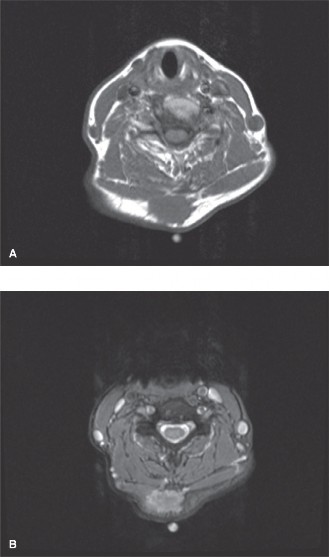

Magnetic Resonance Imaging with and without intravenous gadolinium contrast is the gold standard for evaluating peripheral nerve sheath tumors. The patient underwent a dedicated peripheral nerve MRI protocol of the right forearm.

T1 Weighted Sequences: The mass demonstrated isointense signal relative to the adjacent skeletal muscle. The "split-fat sign" was distinctly visible at the proximal and distal poles of the tumor, representing a rim of normal perineural adipose tissue displaced by the slowly expanding intraneural mass.

T2 Weighted and STIR Sequences: On fluid-sensitive sequences, the mass exhibited a hyperintense signal. A classic "target sign" was observed, characterized by a hyperintense peripheral rim and a centrally hypointense core. This imaging phenomenon corresponds histologically to the peripheral hypocellular, myxoid Antoni B tissue and the central hypercellular Antoni A tissue. Furthermore, the "fascicular sign" was evident, displaying multiple small ring-like structures within the lesion, representing displaced but intact nerve fascicles splayed over the capsule of the tumor.

Post Contrast Sequences: Following gadolinium administration, the mass demonstrated avid, heterogeneous enhancement. The central portion (Antoni A areas) typically enhances more robustly than the peripheral myxoid regions.

Clinical & Radiographic Imaging